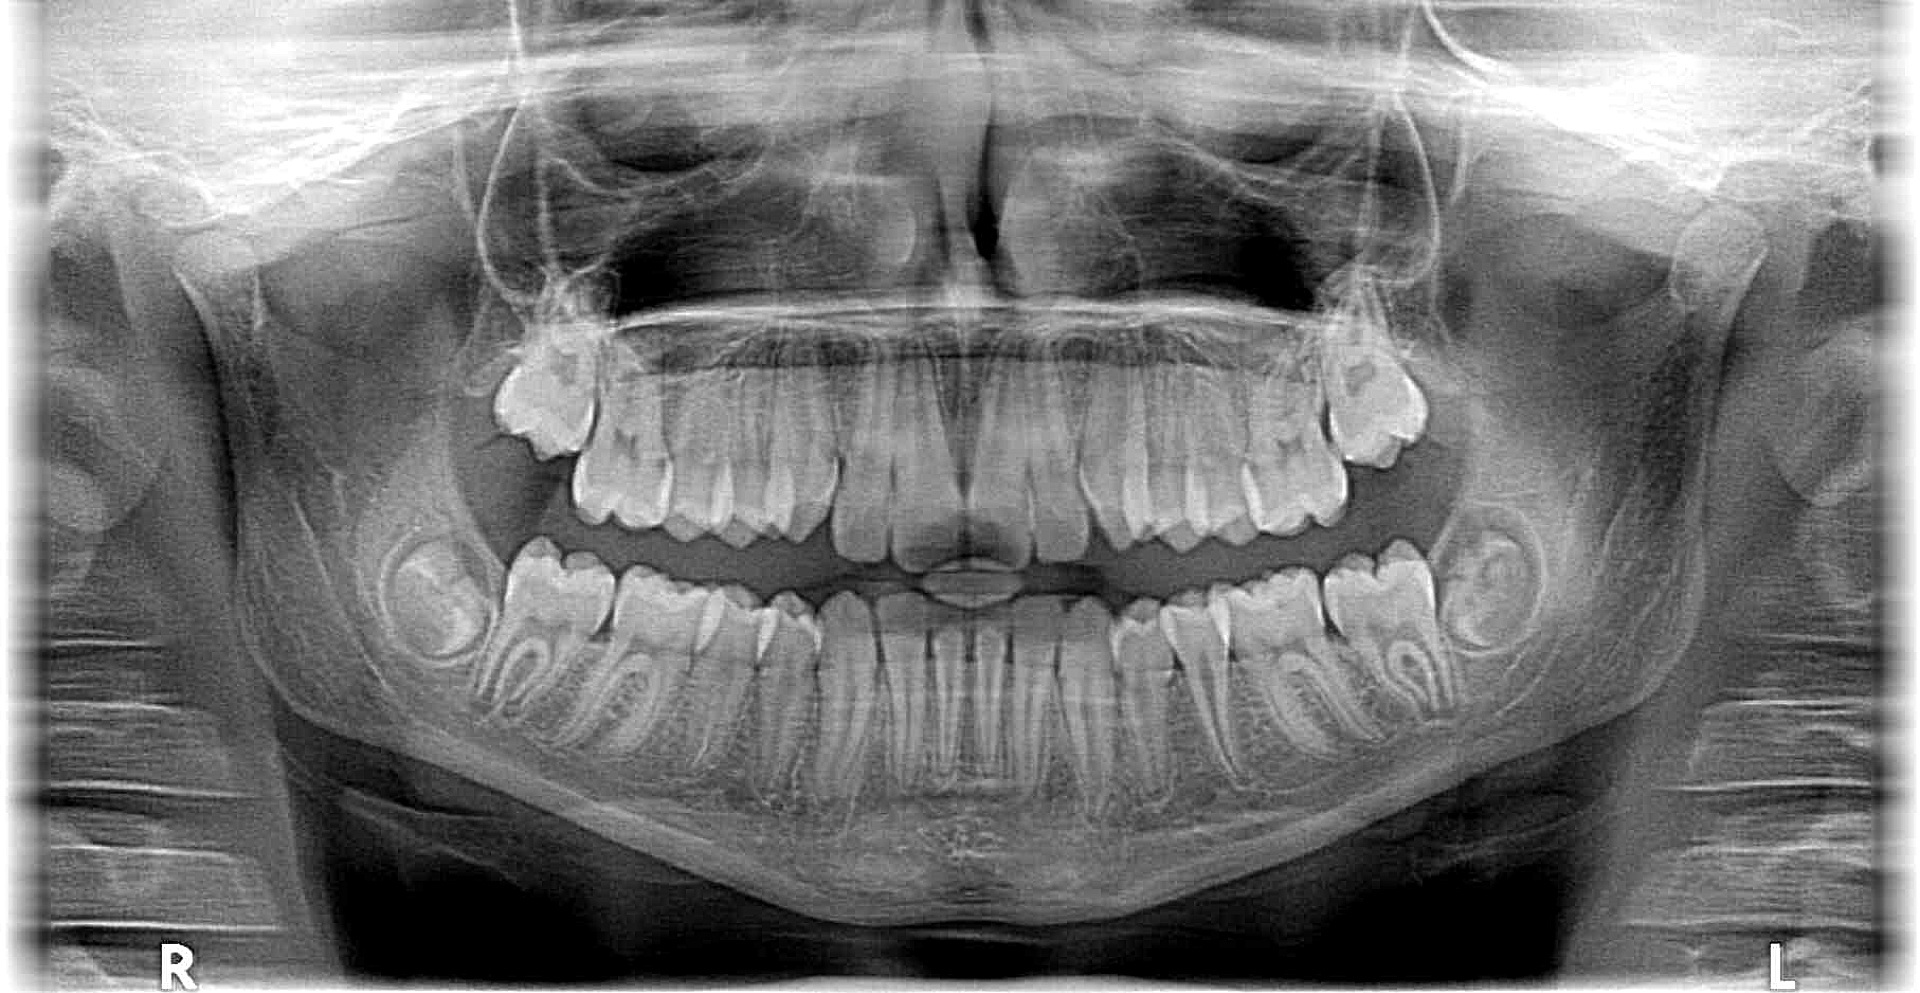

Mit unseren Röntgengeräten der neuesten Generation fertigen wir Aufnahmen an, bei denen Sie als Patient mit einer deutlich geringeren Strahlendosis belastet werden, als dies bei herkömmlichen Geräten der Fall wäre.